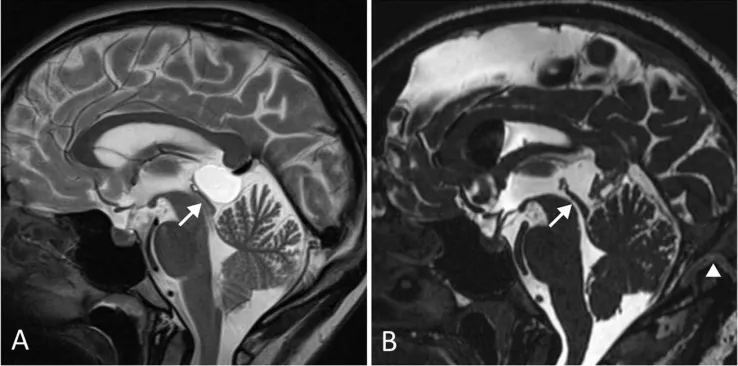

术前(A)影像可见松果体囊肿导致Sylvian大脑导水管狭窄(箭头所示),但无脑积水表现。该患者临床表现为长期且呈进行性加重的头痛。术后(B)影像显示囊肿被完全切除,大脑导水管恢复通畅,患者头痛症状得到完全缓解。